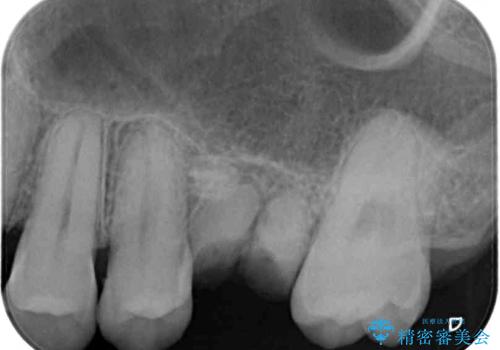

- 前歯のクロスバイトと、大学生のころから放置している虫歯を気にして来院された患者様です。

奥歯の虫歯は抜歯が必要であったので、矯正治療前に抜歯をし、矯正治療と並行してインプラントによる補綴治療を行うこととしました。